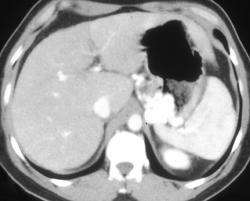

Gastric Lymphoma